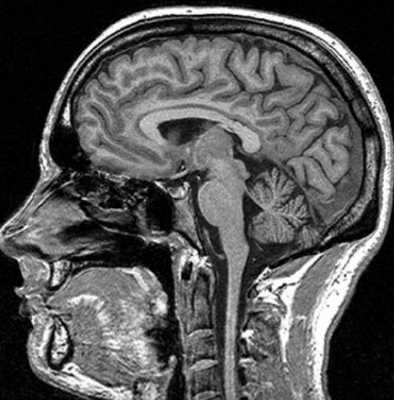

МРТ костей черепа что показывает

Магнитно-резонансная томография базируется на способности магнитного поля изменять состояние атомов водорода в молекулах воды. Процедура информативна относительно мягких тканей, насыщенных жидкостью. Структуры организма с низким содержанием воды на снимках отражаются плохо. МР-томограф фактически «не видит» костную ткань. По этой причине рутинная диагностика переломов включает рентгенографию и КТ (в экстренных, спорных либо сложных ситуациях). При травмах головы стандартное обследование с помощью Х-лучей нередко сочетают с магнитно-резонансной томографией. В зависимости от того, что показывает МРТ костей черепа, дополняют тактику лечения, основанную на результатах КТ. Процедура дает информацию о состоянии мягких структур и влиянии на последние травм.

Диагностическая ценность магнитно-резонансной томографии высока при травмах сложных структур организма (черепная коробка, позвоночник, сочленения). По результатам сканирования диагностируют не сам перелом, а сопутствующие повреждения (разрывы связок, мышц, компрессию тканей и пр.).

На вопрос «Показывает ли МРТ перелом черепа?», врачи дают отрицательный ответ. При травмах головы методом выбора является компьютерная томография. По снимкам оценивают состояние костей, обнаруживают малейшие повреждения последних, кровотечения. Компьютерная томография особенно информативна в первые 48 часов после получения травмы. В дальнейшем изменения в мозге контролируют посредством МР-сканирования.